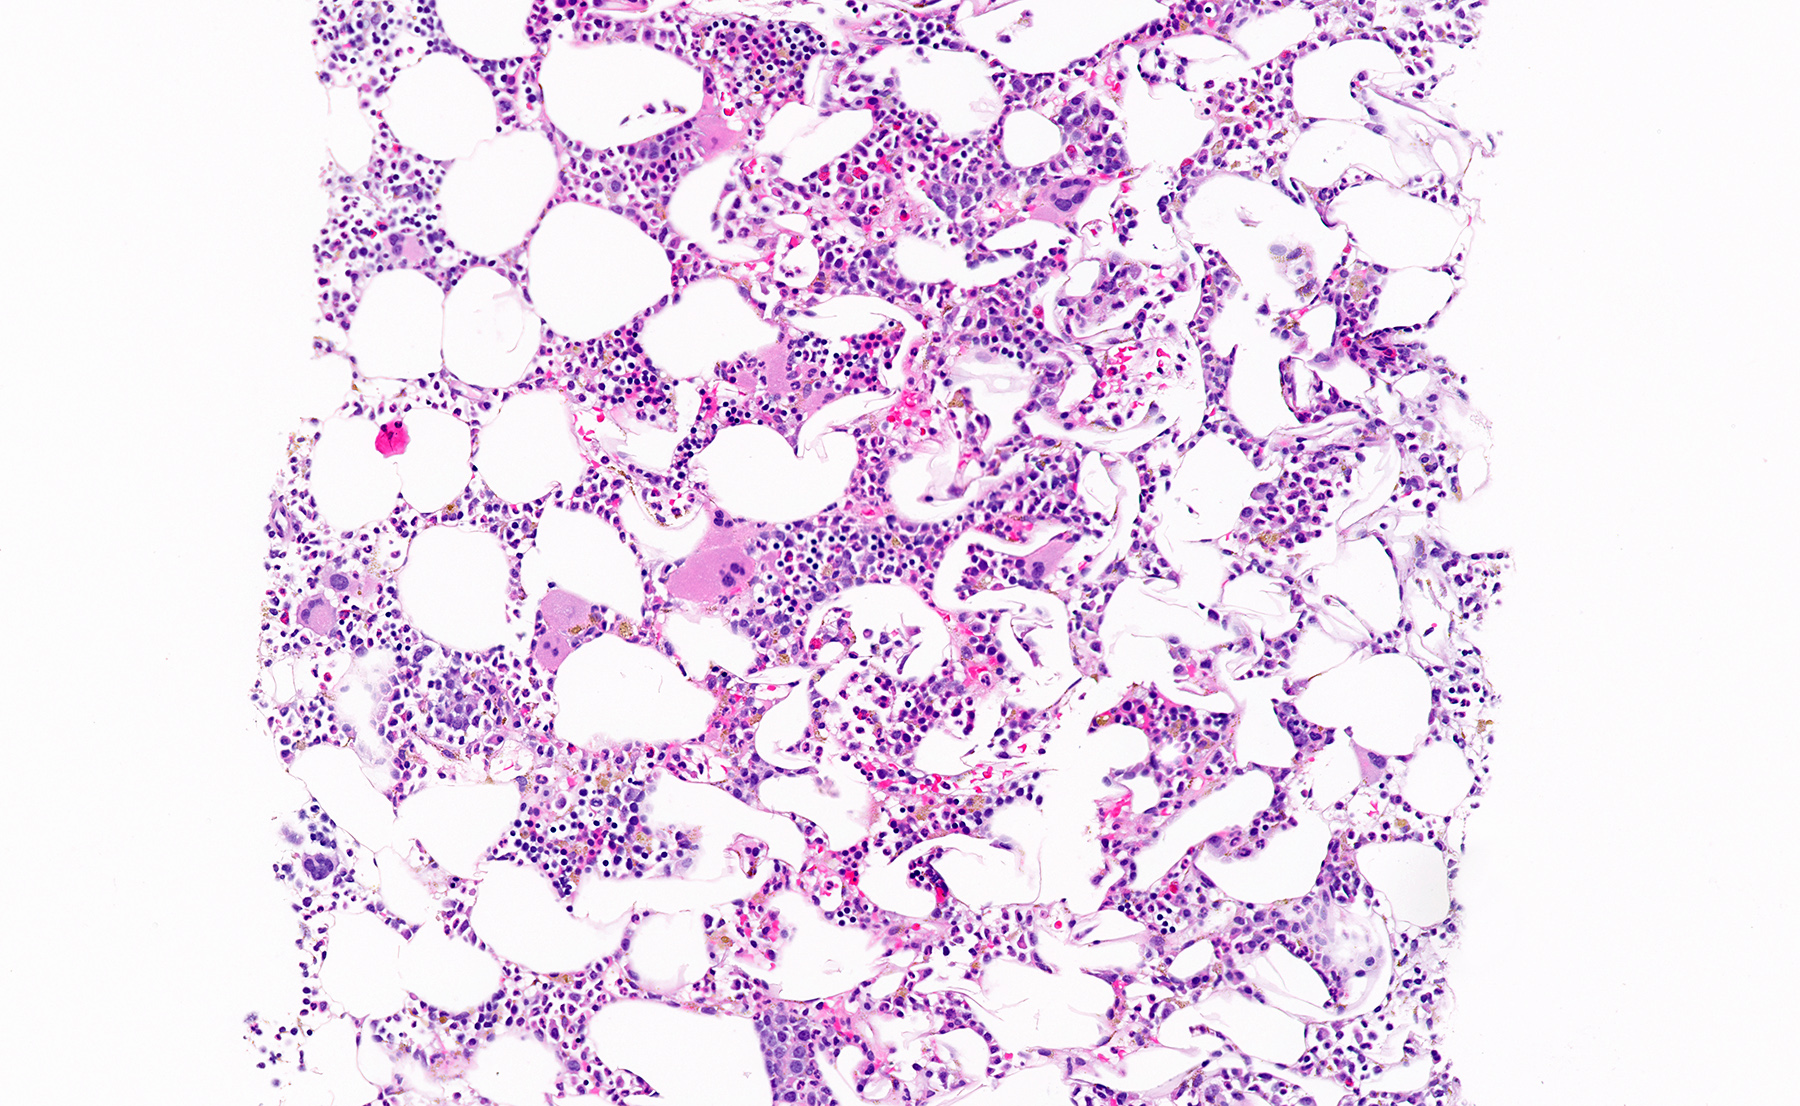

Microscopic (histologic) description

- Mixture of mature adipocytes and extramedullary trilineage hematopoietic cells with full maturation (similar to a hypercellular bone marrow) but often with a markedly increased number of megakaryocytes (Am J Surg Pathol 2006;30:838)

- Calcification, osseous metaplasia and fibrosis can occur

- Rarely may have areas of fibromyxoid degeneration resembling low grade fibromyxoid sarcoma

- Can develop in combination with adrenal cortical tumors, ganglioneuroma, hibernoma, bilateral macronodular adrenocortical disease and congenital adrenal hyperplasia

Microscopic (histologic) images

Contributed by Debra L. Zynger, M.D., Anil Parwani, M.D., Ph.D., O. Hans Iwenofu, M.D., Ph.D. and @ThatGlassTho on Twitter